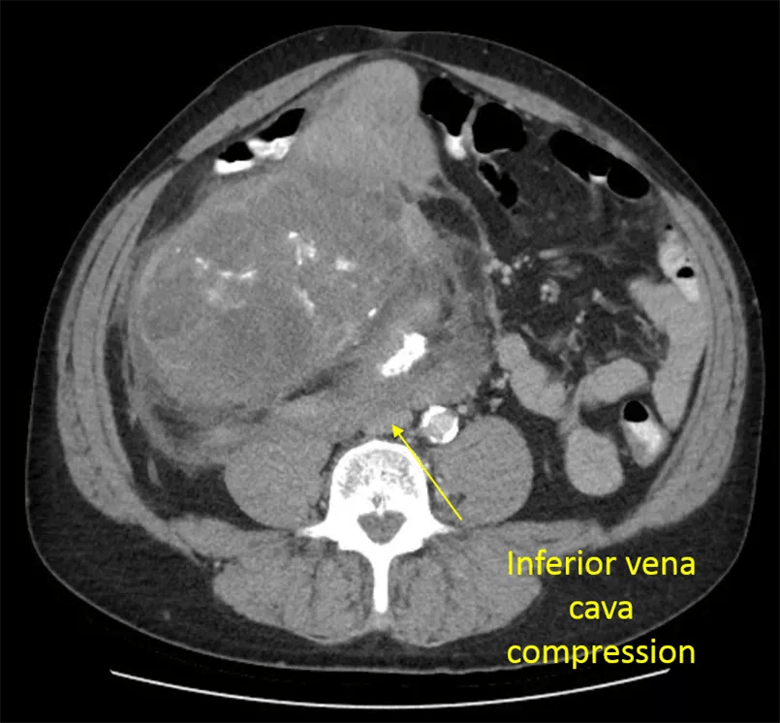

Preoperative CT scan images demonstrate the extent of tumor involving the right kidney, right colon and pancreatoduodenal complex.

There also had been concerns that the patient’s inferior vena cava was involved. Preparing for every possible scenario, Dr. Joyce’s team ensured vascular surgeons were ready to step in if necessary.